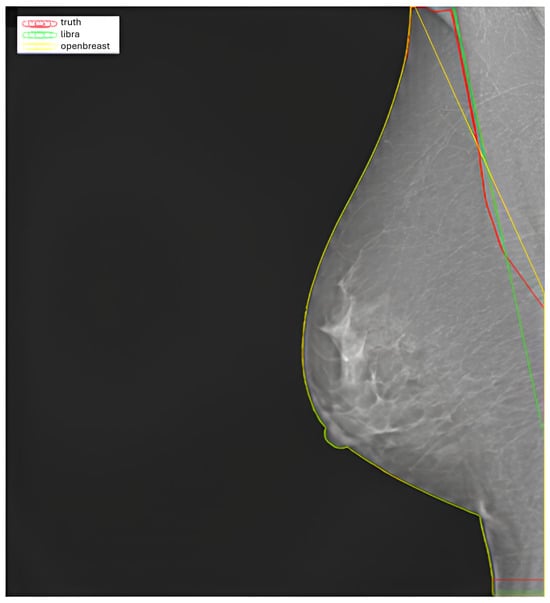

2.2. Segmentation

3.1. Segmentation Results

- Sansone, M.; Marrone, S.; Di Salvio, G.; Belfiore, M.P.; Gatta, G.; Fusco, R.; Vanore, L.; Zuiani, C.; Grassi, F.; Vietri, M.T.; et al. Comparison between two packages for pectoral muscle removal on mammographic images. Radiol. Med. 2022, 127, 848–856. [Google Scholar] [CrossRef] [PubMed]

- Pertuz, S.; Torres, G.F.; Tamimi, R.; Kamarainen, J. Open framework for mammography-based breast cancer risk assessment. In Proceedings of the 2019 IEEE EMBS International Conference on Biomedical & Health Informatics (BHI), Chicago, IL, USA, 19–22 May 2019; IEEE: Piscataway, NJ, USA, 2019; pp. 1–4. [Google Scholar]